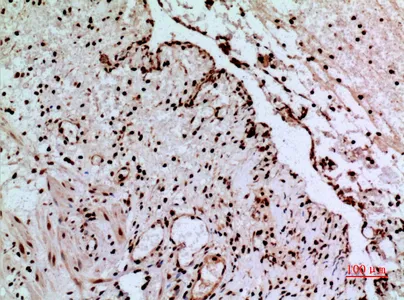

FEN-1 Rabbit Polyclonal Antibody

Cat: APRab10901

Size1:50μl Price1:$118

Size2:100μl Price2:$220

Size3:500μl Price3:$980